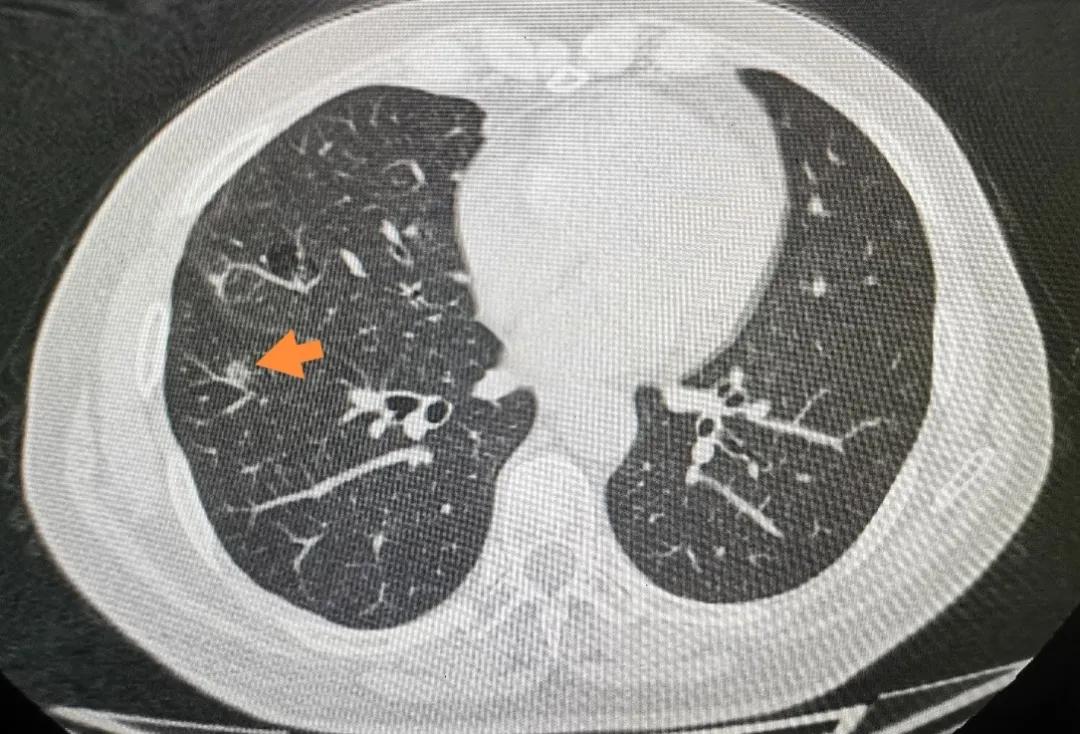

近日,北京积水潭医院胸外科收治一位女性患者, 6月前查体发现肺部结节,位于右肺下叶背段,为3mm磨玻璃结节(GGO),结节无明显实性成分,当时未做治疗,密切随访6月后复查胸部CT,结节进展为5mm结节,GGO伴部分实性成分。

箭头所指即为肿瘤位置